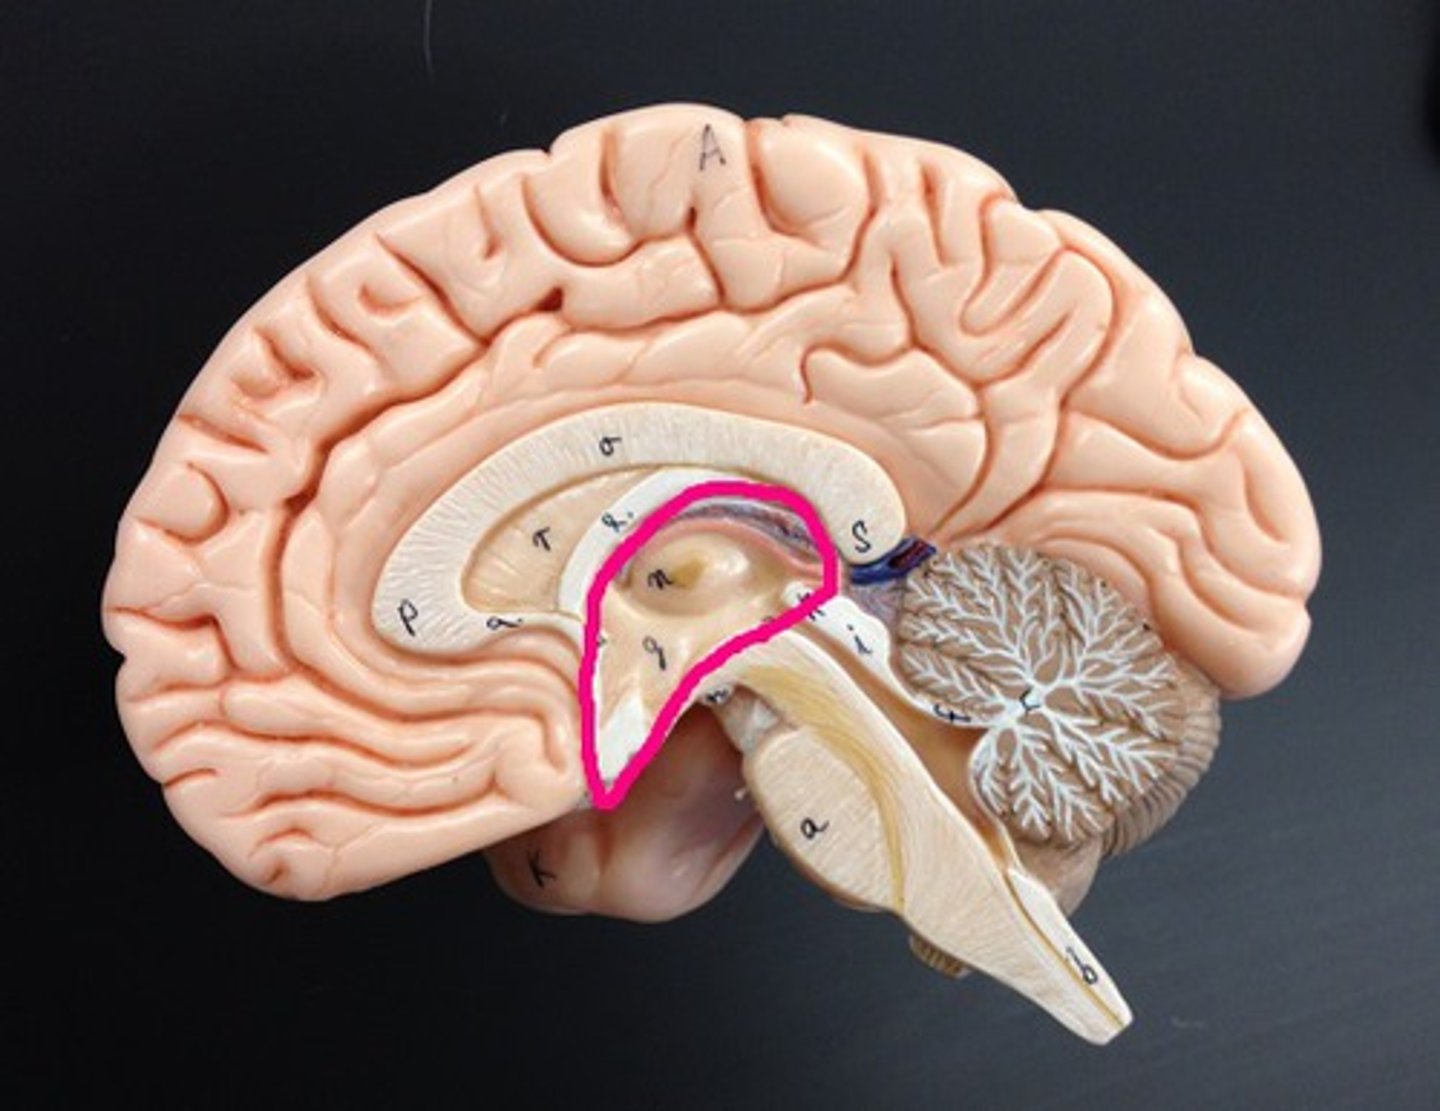

Diencephalon

central part of the brain made up of the thalamus, hypothalamus, and epithalamus

thalamus

•Oval masses of gray matter on lateral sides of third ventricle

•“Relay center” - Receives signals from all conscious senses except olfaction and relays some signals to appropriate part of cortex and filters out other signals distracting from subject of attention (for example, background noise in crowded room)

hypothalamus

a neural structure lying below the thalamus; directs eating, drinking, body temperature; helps govern the endocrine system via the pituitary gland, and is linked to emotion

pituitary gland

endocrine gland at the base of the brain